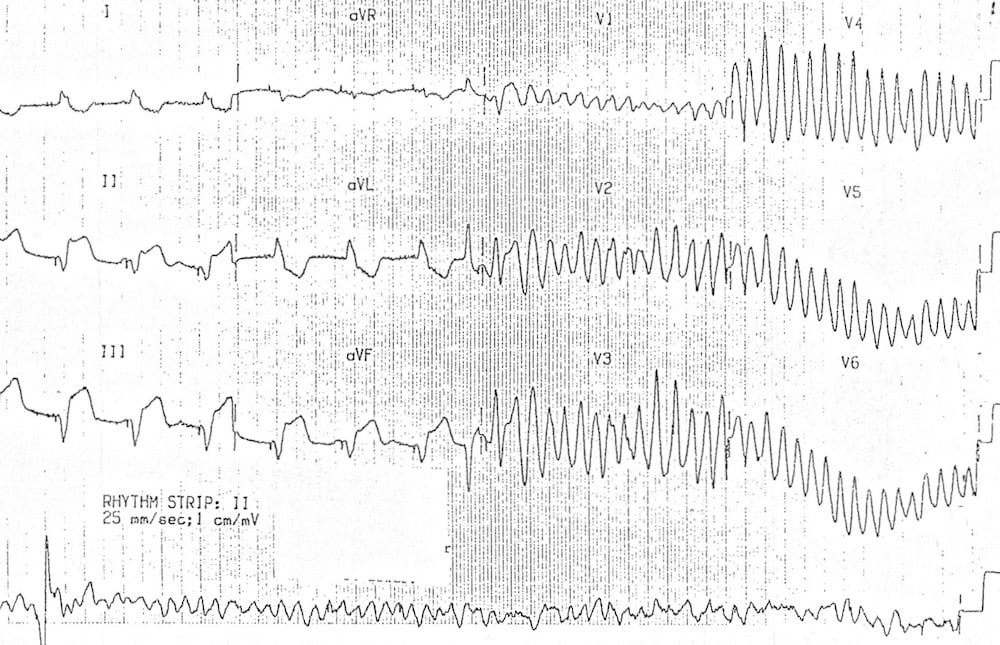

Middle-aged patient presenting with chest pain and diaphoresis. Becomes unresponsive during recording of ECG. Interpret the ECG.

Describe and interpret this ECG

ECG ANSWER and INTERPRETATION

Main Abnormalities

This is a fascinating ECG with multiple abnormalities: